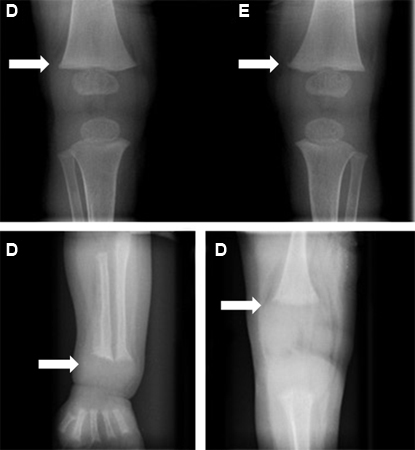

Alterações ósseas (setas) antes (figuras inferiores) e depois (figura superior) do tratamento de raquitismo

Bangalore H, Bisht S, Inusa B. Rickets and tracheobronchomalacia. BMJ Case Reports 2009; doi:10.1136/bcr.01.2009.1422